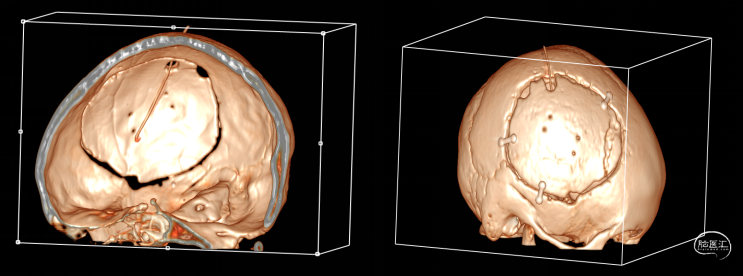

第2次手术后第17天,行颅脑CT检查(如上图),科室讨论仍建议去骨瓣清创,但患者情绪波动明显,拒绝去骨瓣;经协商后行硬膜外脓肿置管引流术。术中根据术前规划,切开颞顶部部分头皮,高速磨钻经骨缘与骨瓣之间磨出骨孔及骨槽,可见骨缘硬脑膜增生,深部硬膜增厚,并伴有灰黄色粘稠脓性液体流出,无明显异味,使用无菌注射器收集脓液约7ml,备细菌培养等检查;置引流管于硬膜外,骨瓣下,反复使用温生理盐水冲洗至水清晰,接负压吸引,及引流袋;术后继续使用万古霉素及美罗培南联合抗炎治疗。术后每日使用万古霉素溶液冲洗硬膜外腔1次。

第3次术后第5天,增强病原微生物高通量基因检测(DNA)显示送检标本内检出表皮样葡萄球菌,未见其他细菌。

第3次术后第9天复查颅脑CT(如上图)。

第3次术后第11天,多学科会诊,停万古霉素及美罗培南,使用头孢曲松+多西环素口服治疗,同日停万古霉素冲洗硬膜外腔。

第3次术后16天,复查颅脑MRI(如上图),硬膜外及皮下异常信号较前明显减少,负压引流管引流不明显,拔除负压引流管,继续使用头孢曲松+多西环素口服联合抗炎治疗。

第3次术后23天,拔管后7天复查颅脑(如上图)。

第3次手术后49天,出院后2周复查颅脑CT情况(如上图),刀口愈合正常,患者回归日常生活、学习。